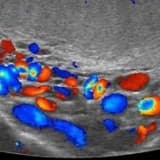

3D görüntüsü kullanmak size ne sağlar?

Hacimsel 3D görüntüden nasıl faydalanabilirsiniz?

•Panoramik ve periapikal röntgen ile pozlanamayan alanları görüntüleyebilirsiniz.

•Çekilen görüntüden koronal, aksiyal, sagital (cross section) kesitler alıp daha detaylı teşhis yapabilirsiniz.

•Implant planlama ve cerrahi klavuz hazırlama için yüksek çözünürlüklü data elde edebilirsiniz.

•Yumuşak doku tespiti, kemik yoğunluğu ölçümü, mandibular kanal mesafesi ölçümü gibi tedavi öncesi planlamalar yapabilirsiniz.

•Tedavi sonrası, protez sonrası ve implant sonrası post operatif kontroller yapabilirsiniz.

•Gömük diş, çatlak, anormal sayıda kanal, kist yayılımı gibi tespitler yapabilirsiniz.

•Alvelolar doku, sinüs, TMJ ile ilgili teşhisler yapabilirsiniz.